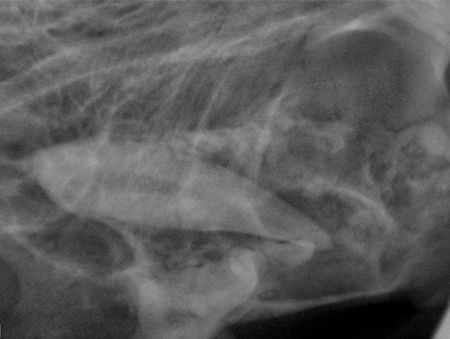

A 2-year-old neutered male domestic longhaired cat is presented for evaluation of a maxillary mass protruding from the space normally occupied by the right maxillary canine, tooth 104 (Photo 1). The swelling is hard throughout its circumference but has a fluctuant portion on its ventral aspect. The patient's history reveals no apparent discomfort, and a pain response is not elicited on palpation. The owners cannot recall whether a tooth was present before the appearance of the swelling. Based on this information, what is your No. 1 rule-out for this swelling?

Photo 1: This 2-year-old cat has a mandibular mass protruding into the vestibule from the space normally occupied by the right maxillary canine.

Neoplasia, particularly odontogenic tumors, must be considered. Infection is possible but unlikely because of the character of the mass and the lack of pain on palpation. The most likely cause is a dentigerous cyst associated with the right maxillary canine tooth. Although definitive diagnosis can only be made with histopathology, dental radiography is extremely valuable in determining the cause in these cases. Photo 2 shows the tooth displaced caudally and toward the midline within the relatively lucent right maxilla.